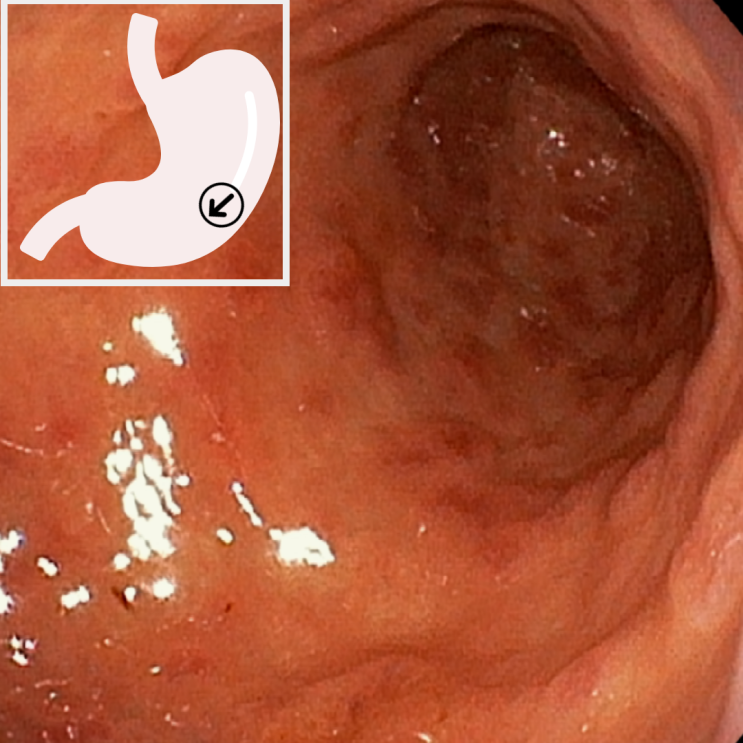

고혈압 환자분의 경동맥 초음파 결과